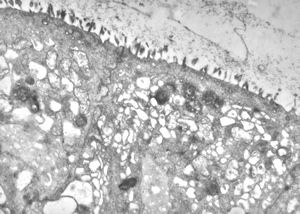

normal mucosa - jejunum - microvilli(anchored core rootlets)

normal mucosa - jejunum - microvilli